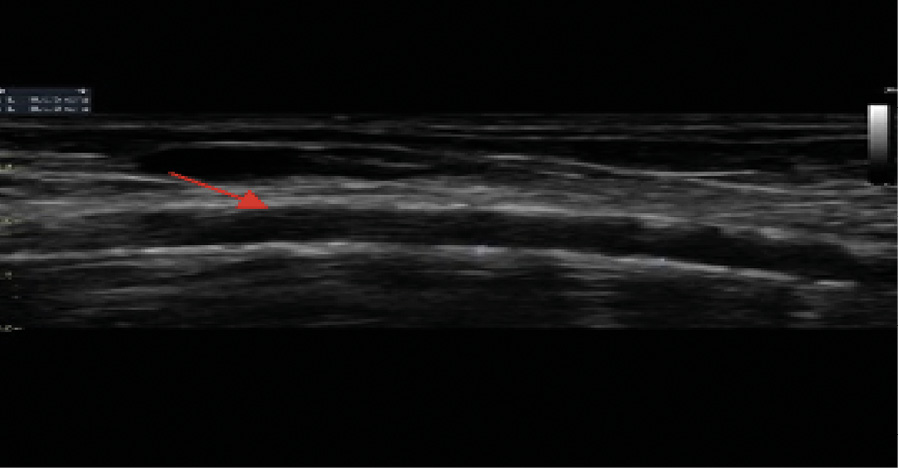

При измерении лодыжечно-плечевого индекса (ЛПИ) доплеровский сигнал не исчезал даже в случае нагнетания давления в манжете более 300 мм рт. ст. по трем измеряемым артериям. По левой окклюзированной в проксимальном сегменте задней большеберцовой артерии получен показатель 1,3, что отражает значимую кальцификацию сосудистой стенки. Распространение кальциноза наблюдалось и на пальцевые артерии, что сопровождалось несжимаемостью этих артерий, свойственной пациентам с ХБП, получающим заместительную почечную терапию, или пациентам после трансплантации почки. По данным ультразвукового дуплексного сканирования внечерепных отделов брахиоцефальных артерий, в устье левой внутренней сонной артерии выявлена кальцинированная атеросклеротическая бляшка (стеноз 20%). Ультразвуковое дуплексное сканирование артериовенозной фистулы левой верхней конечности: эхографические признаки кальциноза (рис. 5) с симптомами ускоренного кровотока в бассейне левой плечевой артерии (230 см/с) в сравнении с контрлатеральной плечевой артерией (77 см/с). Избыточное шунтирование артериальной крови по фистуле напрямую в венозное русло, предположительно, может способствовать развитию ригидности сосудистой стенки, что обусловлено изменением кинетических характеристик движущейся крови (давления, объема, скорости), иными словами, «напряжением сдвига». Вследствие повышенного воздействия на механорецепторы эндотелия могут активироваться патологические процессы, направленные на активацию сосудистой кальцификации у нашего пациента.

Рис. 5. Эхограмма пациента Т. Ультразвуковое дуплексное сканирование артериовенозной фистулы левой верхней конечности. Обызвествление стенок плечевой артерии артериовенозной фистулы левой верхней конечности (указано стрелкой)